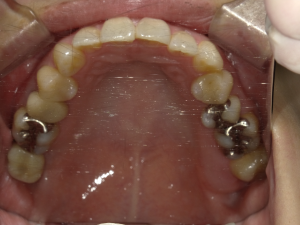

インプラント治療(左上5ソケット・GBR 右上2左上13GBR)

| 年代・性別 | 50代・男性 |

| 主訴 | 入れ歯だと咬めなくてつらい。 |

| 部位 | 上顎②1①2③4⑤Br |

| 治療期間 | 約9ヶ月 |

| 費用 | ¥1,794,100(税込) |

| 副作用・リスク |

|